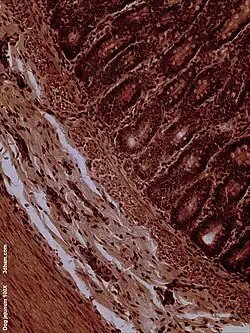

Dog jejunum (magnified 100-fold)

The jejunum contains very few Brunner's glands (found in the duodenum) or Peyer's patches (found in the ileum). However, there are a few jejunal lymph nodes suspended in its mesentery. The jejunum has many large circular folds in its submucosa called plicae circulares that increase the surface area for nutrient absorption. The plicae circulares are best developed in the jejunum.

There is no line of demarcation between the jejunum and the ileum. However, there are subtle histological differences:

- The villi of the jejunum look like long, finger-like projections, and are a histologically identifiable structure.

- While the length of the entire intestinal tract contains lymphoid tissue, only the ileum has abundant Peyer's patches, which are unencapsulated lymphoid nodules that contain large numbers of lymphocytes and immune cells, like microfold cells.